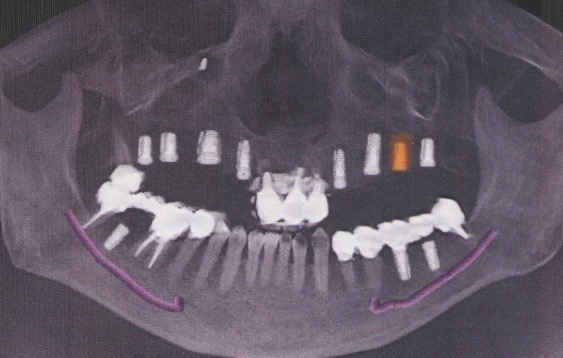

- 10年前から他の歯科医院にて入れ歯治療を受けたが、見た目が良くない・噛めないと・喋りにくいとのことで再治療を希望された。アングルクラスⅢであった。左右上奥歯がない。

- 上顎左右側にインプラントを8本し、

- 入れ歯+オールセラミックのボーンアンカーブリッジにて被せ物を行なった。

- 下顎臼歯に3本のインプラントを入れ、オールセラミッククランにて被せ物を行なった。